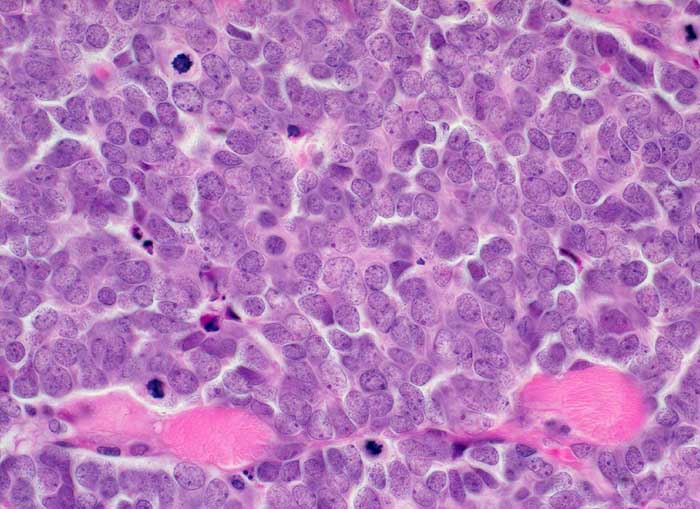

Das Merkelzellkarzinom ist ein neuroendokrines Karzinom ausgehend von den Merkelzellen der Haut. Die Ausstriche sind zellreich. Die monomorphen zytoplasmaarmen Zellen liegen einzeln oder in lockeren Verbänden. Die Kerne sind fragil, rund bis oval und hyperchromatisch. Das Chromatin zeigt ein Pfeffer und Salz Bild. Die Unterscheidung von der Metastase eines kleinzelligen Bronchuskarzinoms oder von einem Lymphom kann immunzytochemisch erfolgen. Merkelzellkarzinome zeigen eine charakteristische punktförmige zytoplasmatische Positivität für CK20 und sind negativ für TTF1, BerEP-4 und CD45.